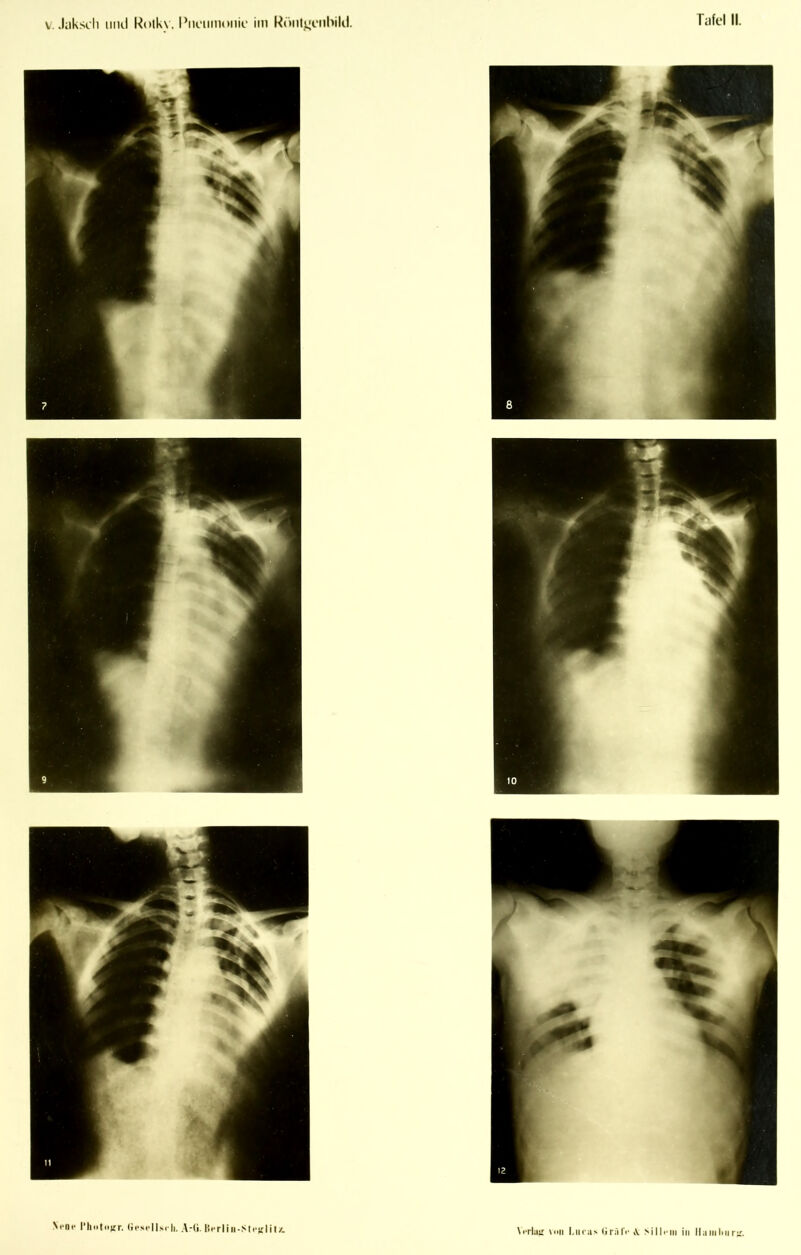

Die Pneumonie im Röntgenbilde ... : mit 59 Röntgenbildern auf 10 Tafeln und 10 Skizzenblättern / von R.v. Jaksch und H. Rotky.

Credit: Die Pneumonie im Röntgenbilde ... : mit 59 Röntgenbildern auf 10 Tafeln und 10 Skizzenblättern / von R.v. Jaksch und H. Rotky. Source: Wellcome Collection.